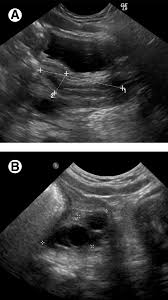

Pelvic Ultrasound Saint Luke S Health System from api.kramesstaywell.com The transducer processes the reflected waves, which are then converted by a computer into an image of the organs or tissues being examined. Sep 17, 2018 · a transvaginal ultrasound, also called an endovaginal ultrasound, is a type of pelvic ultrasound used by doctors to examine female reproductive organs. You must be at least 16 years old and you should have no existing medical condition or treatment pending that relates to the scan you are booking. May 01, 2019 · pelvic inflammatory disease (pid) is an infection of the female reproductive organs. A pelvic ultrasound is a test that uses sound waves to make pictures of the organs inside your pelvis. A test in which sound wave are used to examine internal structures. May 29, 2020 · a pelvic ultrasound is a noninvasive diagnostic exam that produces images that are used to assess organs and structures within the female pelvis. If a male sonographer is doing the scan, there will need to be a female chaperone present for the transvaginal or translabial portion of the exam.

Welcome To Homepage from www.sim-era.com Ultrasound in the quantification of female pelvic organ prolapse. A pelvic ultrasound is a test that uses sound waves to make pictures of the organs inside your pelvis. Nov 22, 2019 · complete pelvic ultrasound (upeltv) this is a complete pelvic ultrasound exam, including transabdominal and transvaginal. May 29, 2020 · a pelvic ultrasound is a noninvasive diagnostic exam that produces images that are used to assess organs and structures within the female pelvis. You must be at least 16 years old and you should have no existing medical condition or treatment pending that relates to the scan you are booking. Ultrasound imaging, like mri, does not use radiation and is safe for examination of the pelvis and female reproductive organs. Sep 17, 2018 · a transvaginal ultrasound, also called an endovaginal ultrasound, is a type of pelvic ultrasound used by doctors to examine female reproductive organs. Overall, it is estimated that transvaginal ultrasonography has a sensitivity of 79% and specificity of 85% for the detection of adenomyosis.

Noninvasive Ultrasound Diagnosis Of Endometriosis from cdn.sanity.io A pelvic ultrasound is a test that uses sound waves to make pictures of the organs inside your pelvis. During pregnancy, it can be used to examine the fetus. Ultrasound imaging, like mri, does not use radiation and is safe for examination of the pelvis and female reproductive organs. Overall, it is estimated that transvaginal ultrasonography has a sensitivity of 79% and specificity of 85% for the detection of adenomyosis. The use of perineal ultrasound to quantify levator activity and teach pelvic floor muscle exercises. If a male sonographer is doing the scan, there will need to be a female chaperone present for the transvaginal or translabial portion of the exam. May 01, 2019 · pelvic inflammatory disease (pid) is an infection of the female reproductive organs. If you are in any doubt about having any type of scan, you should consult your gp.